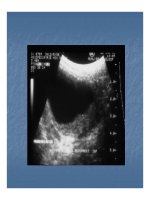

 Đụng dập dày thành khu trú.Đụng dập dày thành khu trú.

 Mất liên tục thành BQ.Mất liên tục thành BQ.

 Máu tụ khoang dưới phúc mạc, quanh bàng quang Máu tụ khoang dưới phúc mạc, quanh bàng quang 

vỡ BQ ngoài phúc mạc.vỡ BQ ngoài phúc mạc.